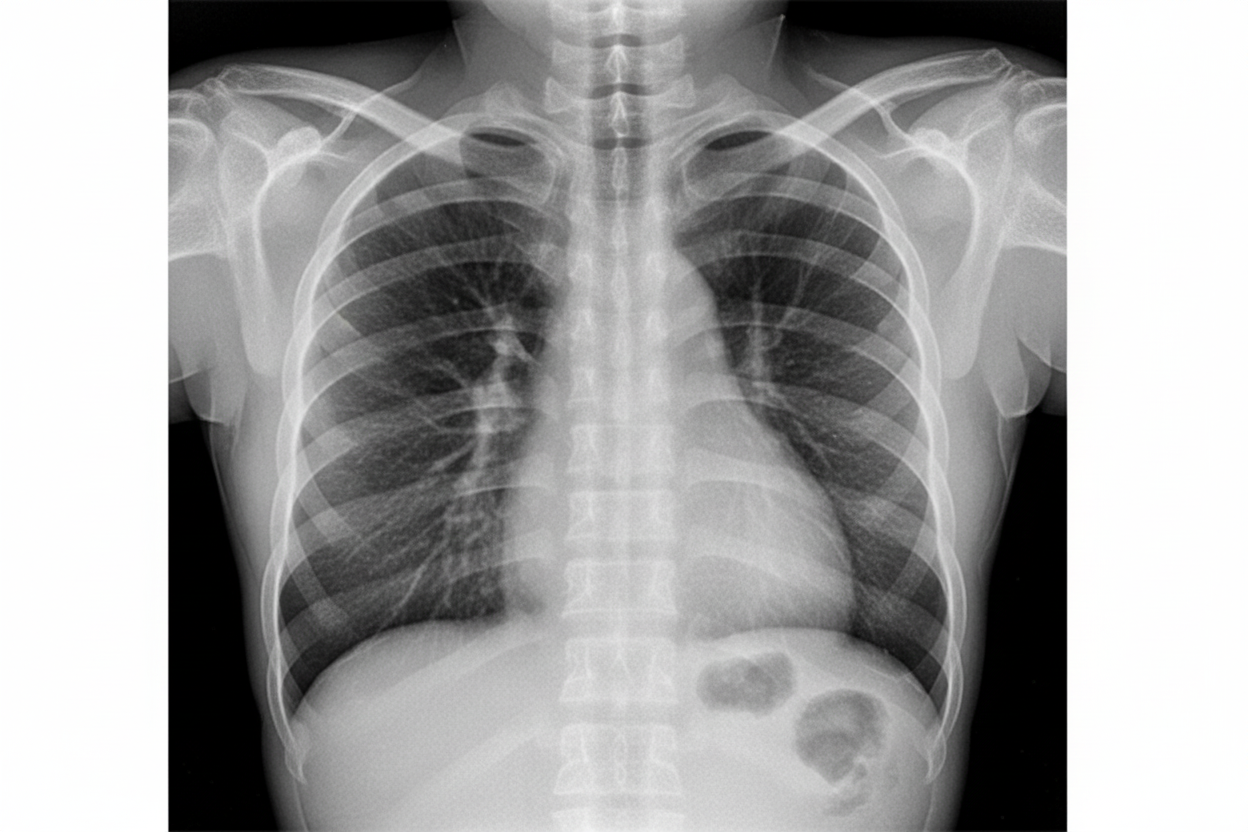

What is the likely diagnosis based on the provided chest X-ray?

Explanation: ***Tetralogy of Fallot (TOF)*** - Classic **"boot-shaped heart"** (coeur en sabot) appearance on chest X-ray with **upturned apex** due to right ventricular hypertrophy and **concave main pulmonary artery segment**. - **Decreased pulmonary vascularity** (oligemia) is characteristic due to pulmonary stenosis limiting blood flow to the lungs. *Total anomalous pulmonary venous connection (TAPVC)* - Typically shows the **"snowman sign"** or **"figure-of-8"** configuration on chest X-ray due to dilated vertical vein and left innominate vein. - Associated with **increased pulmonary vascularity** and **cardiomegaly**, not the boot-shaped heart seen here. *Ventricular septal defect (VSD)* - Chest X-ray shows **increased pulmonary vascularity** due to left-to-right shunting and **cardiomegaly** from volume overload. - Heart shape remains **normal** without the characteristic boot appearance or decreased pulmonary flow. *Atrial septal defect (ASD)* - Presents with **cardiomegaly** and **prominent pulmonary vasculature** due to increased pulmonary blood flow from left-to-right shunting. - **Right heart enlargement** may be present but lacks the specific boot-shaped configuration and pulmonary oligemia.